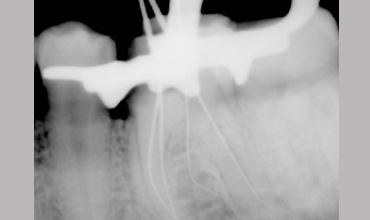

Management Of Radix Entomolaris In Mandibular First Molar